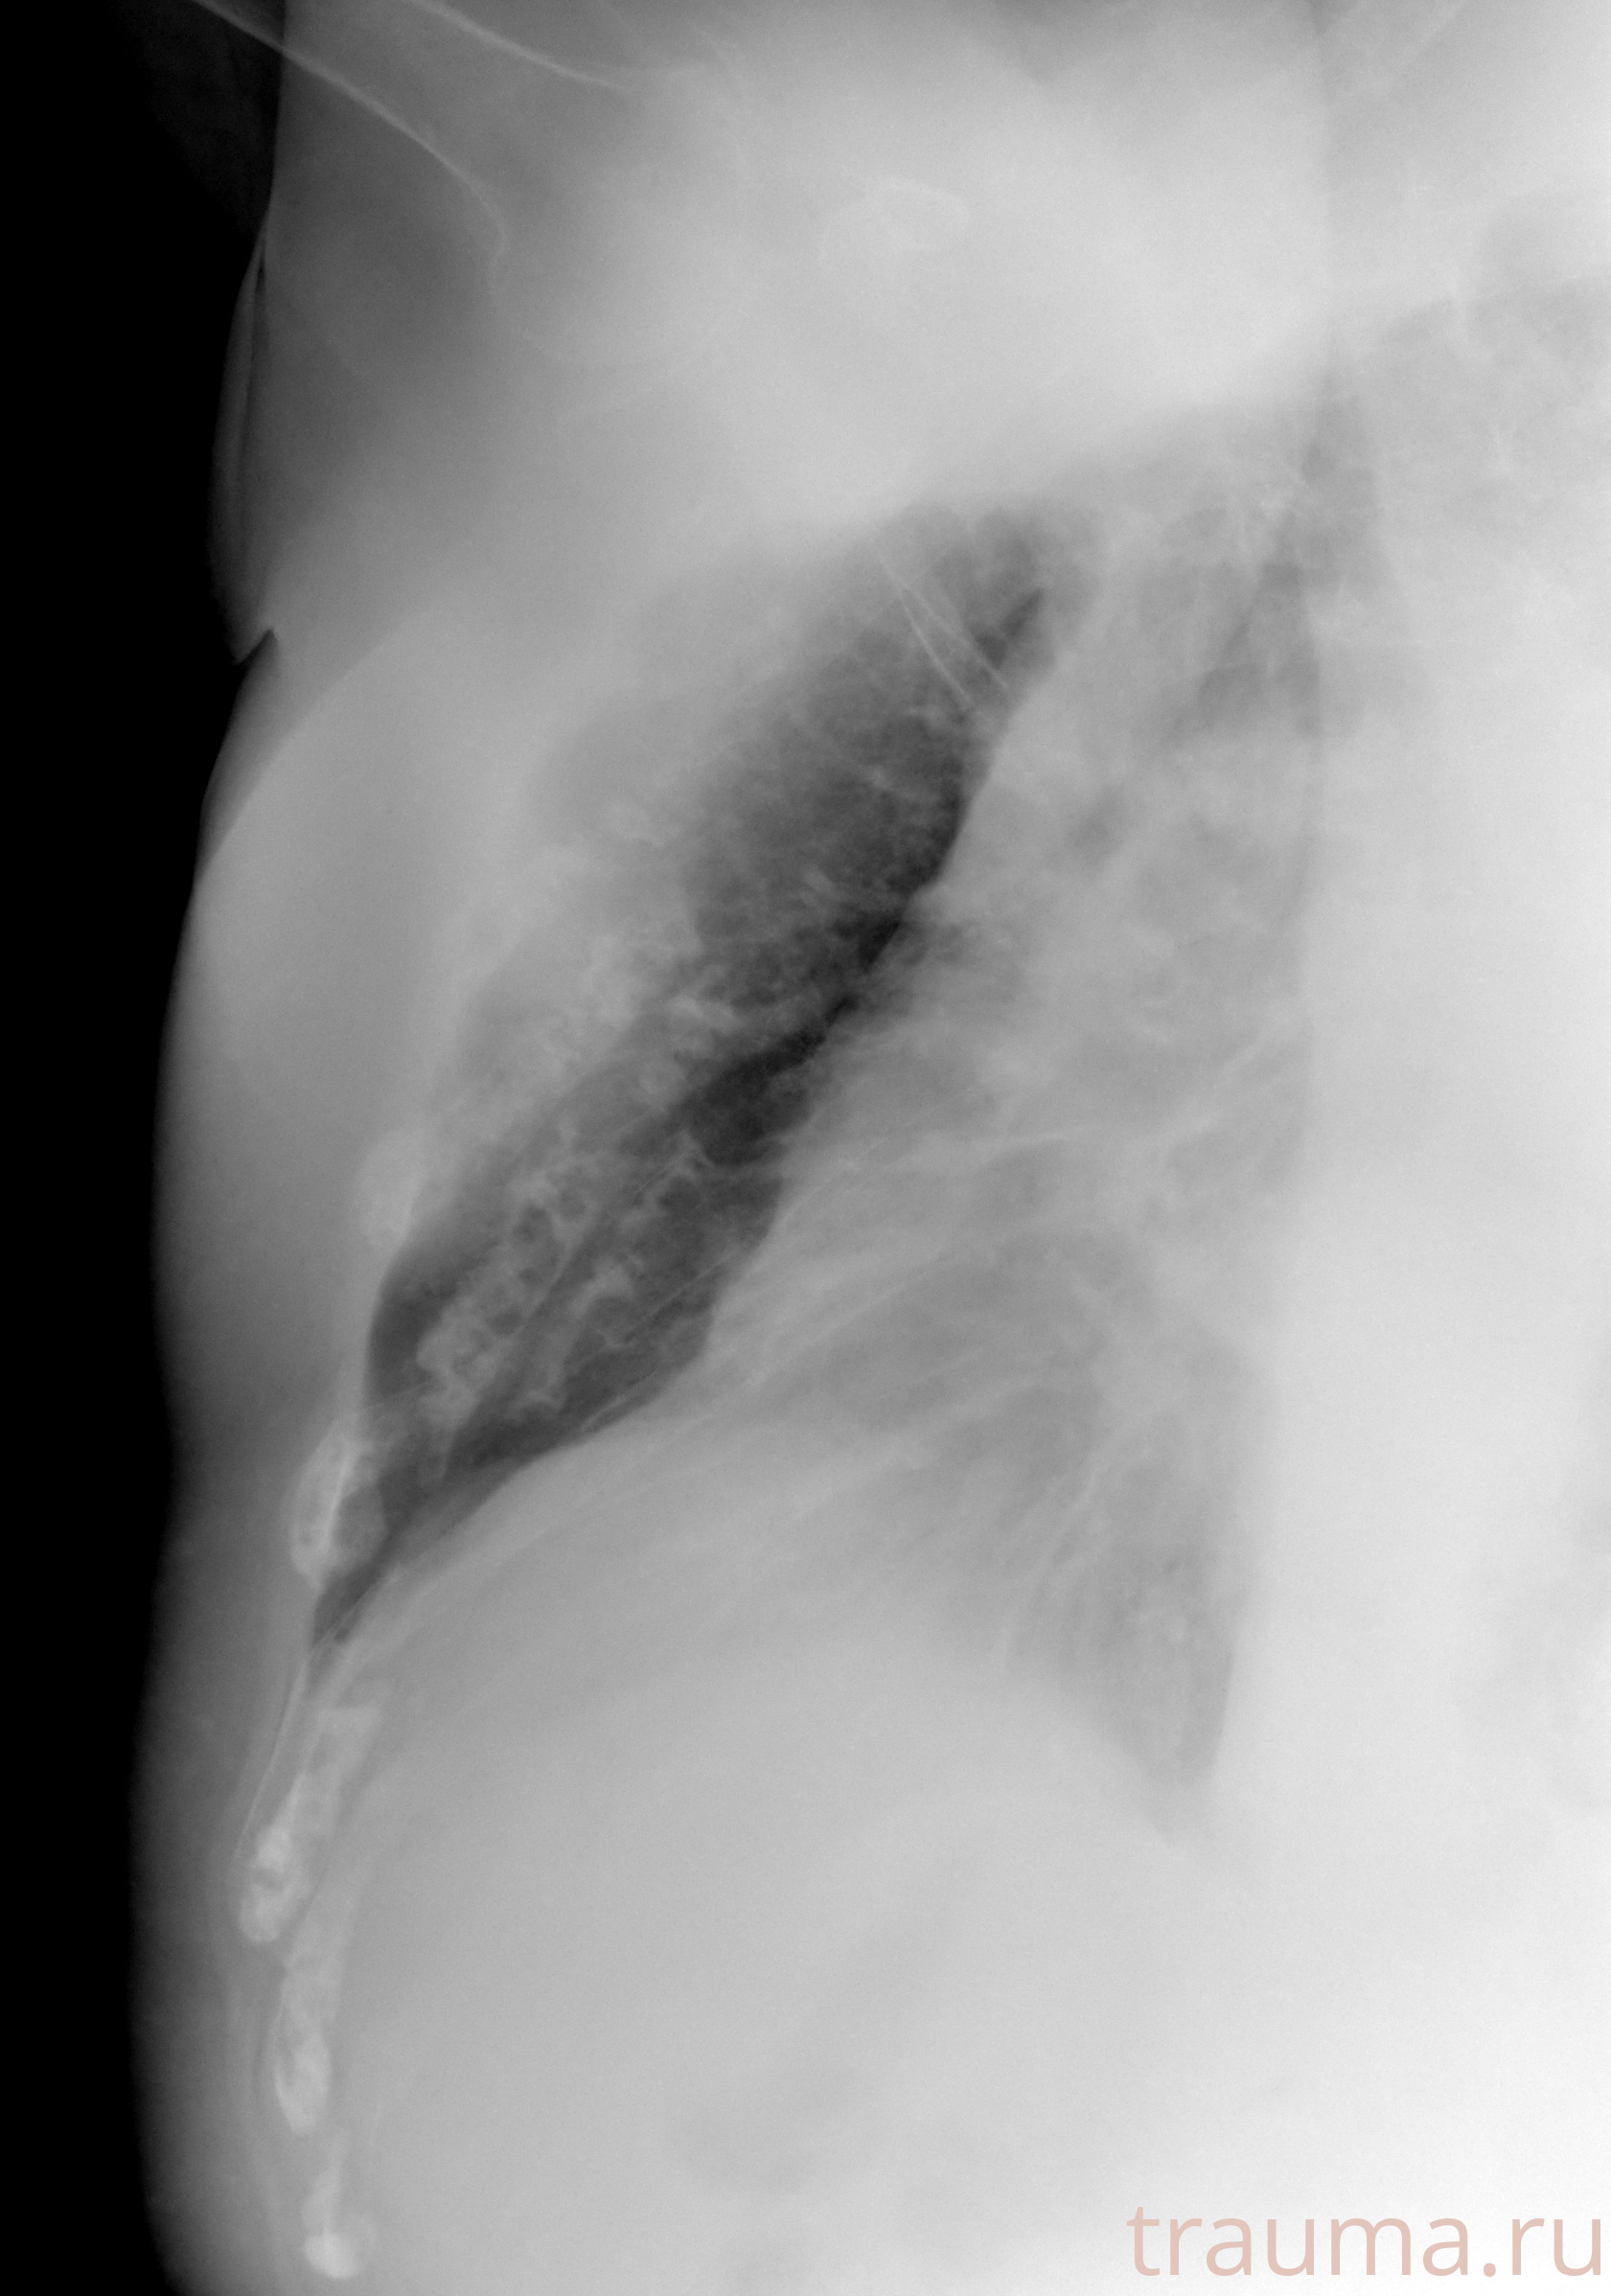

Рентген на дому: по вашему адресу приезжает врач-рентгенолог, травматолог-ортопед с мобильным рентгеновским аппаратом, проводит диагностику травмы или заболевания, делает необходимые рентгенограммы, дает рекомендации по дальнейшему лечению. Получить качественные снимки в домашних условиях возможно благодаря уникальной методике, разработанной МосРентген Центром для института  Склифосовского

при переломе шейки бедра и пневмонии от компании МосРентген Центр - партнера Института имени Склифосовского